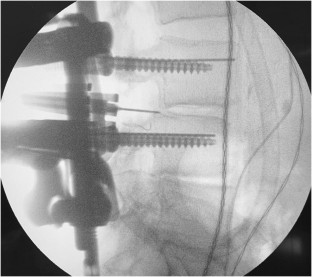

Fig. 1

Fig. 2

Fig. 3

Fig. 4

Fig. 5

Fig. 6

2. Percutaneous pedicle screw placement on the contralateral side, K-wire left without screws on the side of the decompression to keep the tubular channel with the maximal possible working space.